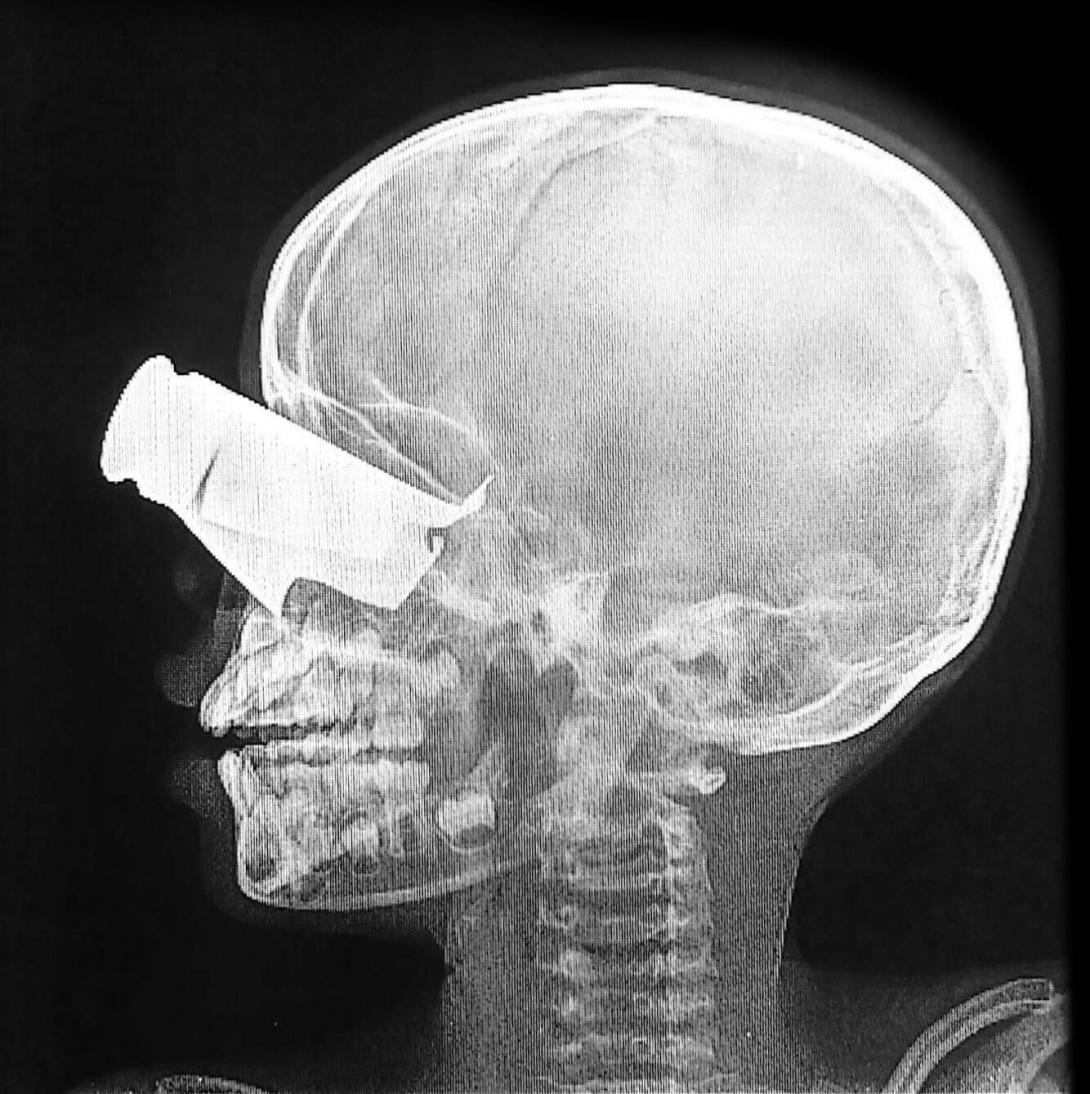

“Entre los pacientes que recibimos, un niño de 9 años llegó con una gran herida de metralla en el ojo, extensas fracturas faciales y dos dedos amputados. Presentaba fuertes dolores y estaba expuesto al polvo tras un largo viaje para llegar al centro. Incluso con una atención óptima, es probable que sufra una discapacidad a largo plazo. Fue trasladado a Yamena para recibir tratamiento adicional”, afirma Virginia Moneti, coordinadora médica de nuestro proyecto en Tine. Nuestros equipos en Zalingei, Darfur Central, también trataron a 29 pacientes este mes tras varios ataques, incluidos al menos 8 civiles.